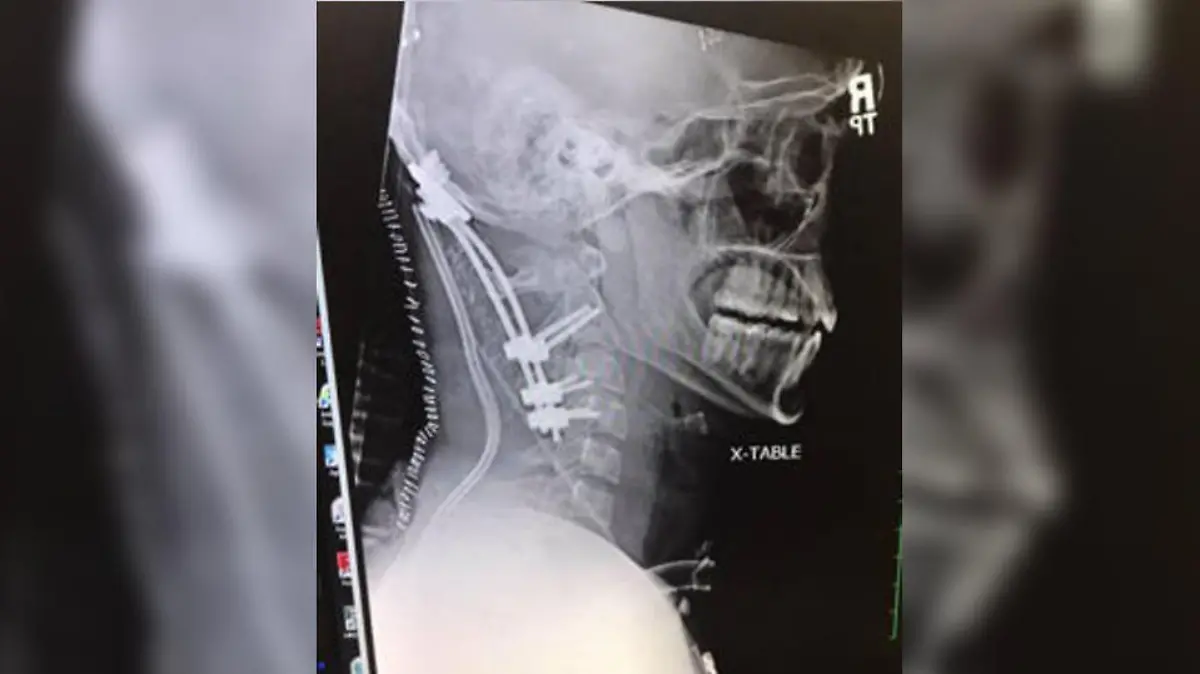

Bei Brocks Verletzung mussten die Chirurgen schnell handeln: In einer aufwändigen Operation brachten sie Metallschrauben an seinem Schädel und seiner Wirbelsäule an und verbanden sie mit einer Stange. So gelang es ihnen, Brock zu stabilisieren und sein Leben zu retten. Dass die Operation gut ausging, dafür ist er endlos dankbar: "Ich bin einfach froh, hier sein zu können. Das ist alles, was zählt", sagt er.